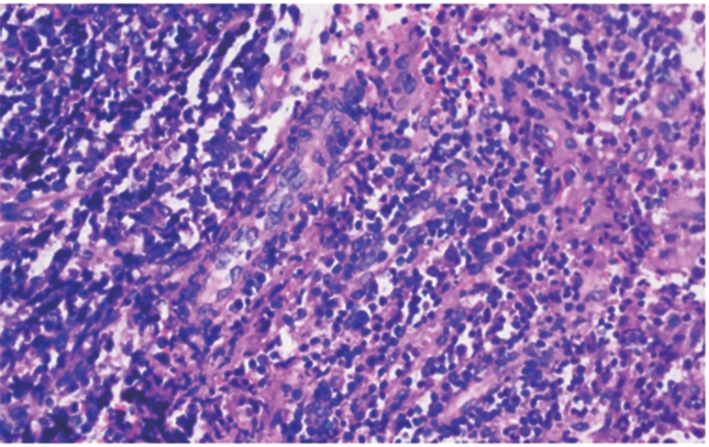

摘要:目的 通过转录组测序(RNA sequencing,RNA-Seq)和TMT蛋白质组学技术,筛选差异表达的基因及蛋白,探讨脊髓损伤后复杂的病理机制。方法 50只雌性C57BL/6小鼠随机分为假手术组、模型组,每组25只。采用钳夹法在腰1处制备小鼠脊髓损伤模型,14 d后进行取材。采用后肢运动功能评分(basso mouse scale,BMS)评估小鼠后肢运动功能变化;HE染色法观察脊髓损伤区病理形态学变化;RNA-Seq技术筛选差异基因;TMT蛋白组学分析筛选差异蛋白;结合2种测序技术筛选变化趋势吻合的mRNA和蛋白并进行生物信息学分析。结果 与假手术组相比,模型组中BMS评分明显降低(P<0.05);HE染色显示脊髓损伤区域结构疏松紊乱,出现空洞,细胞核固缩,炎性浸润严重,神经元坏死;RNA-Seq共筛选出565个差异mRNA,其中545个上调,20个下调,TMT蛋白组学共筛选出339个差异蛋白,其中278个上调,61个下调;2种测序的聚类热图显示2组样本的表达模式差异大;韦恩图分析获得83个趋势上调的mRNA或蛋白;蛋白互作(protein-protein interaction,PPI)网络分析获得11个核心靶点;GO富集分析显示分子功能或生物过程主要在免疫应答、溶酶体途径、细菌反应、液泡裂解等方面;KEGG富集通路主要在结核病变、溶酶体、吞噬小体途径等通路。结论 本研究筛选出的11个mRNA或蛋白可能是调控脊髓损伤病理过程的核心靶点,病理机制可能与免疫应答途径、溶酶体和吞噬小体等通路密切相关。